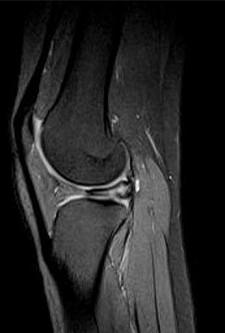

问题 男,16岁,左膝关节有过外伤,现肿痛,有膝关节弹响,请结合MRI检查,选出最可能的诊断 ( )

选项 A、关节结核 B、风湿关节炎 C、滑膜炎 D、半月板撕裂 E、化脓性关节炎

答案 D